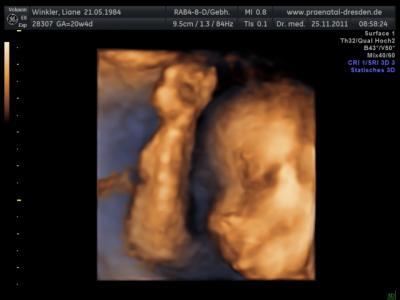

Wir waren heut früh bei der FD. War super spannend. Haben einen ganz lieben Arzt erwischt. Der hatt uns alles ganz genau erklärt und unser betsimmt teilweise blöden Fragen, ganz geduldig beantwortet. Ist alles dran und dort wo es hingehört. Besonders niedlich fand ich, wo er anfing, die kleinen Fingerchen zu zählen. Und zu guter letzt gabes noch das von uns so lang erwartete Outing! Wir bekommen ein Mädchen !!!!!!!!!!!!! Es ist schon stolze 345 g schwer und ganze 22 cm groß! Als Bonus gab es noch eine CD mir vielen süßen Bildchen von unserer Püpi. Wir freuhen uns riesig und am WE kommen meine und seine Eltern zu uns, da wollen wir es ihnen erzählen! Bin schon ganz gespannt, wie alle reagieren. LG Kuschelwundertüte

Bild zu FD und Outing!!! :o)))) - Forum für April - Mamis